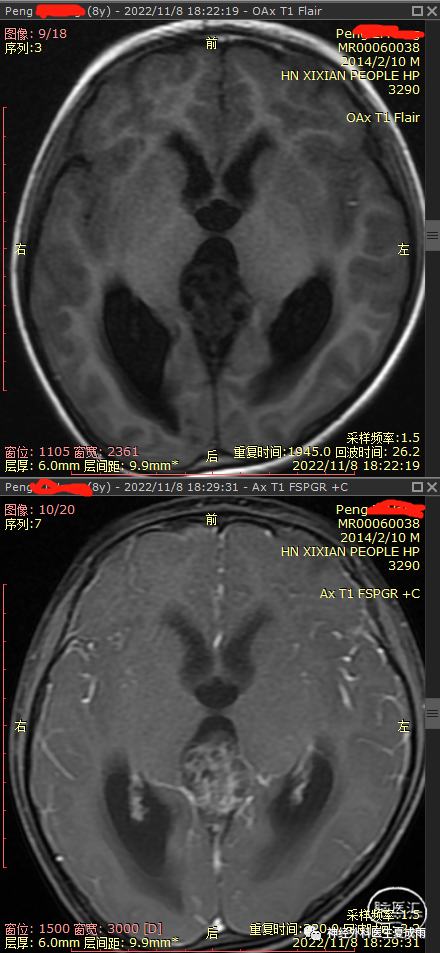

外院磁共振⏬

根据术前影像有钙化,强化不均匀,无尿崩,以及血清AFP增高,考虑为非生殖细胞瘤的生殖细胞肿瘤,建议首选行肿瘤切除术。